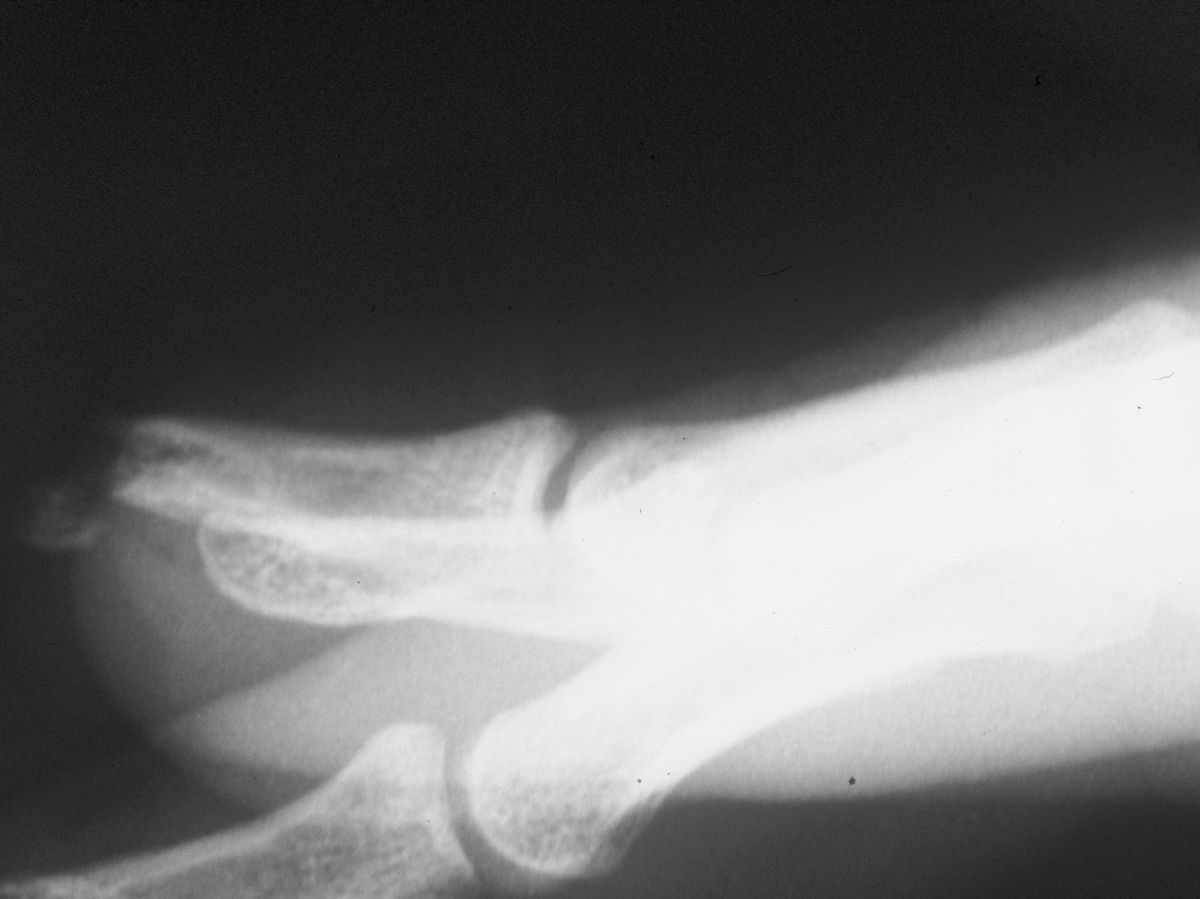

| Case

4. A dog bit off this young man's index fingertip. Although the PA Xray looks as though the bone was kept, additional views show an amputation through the tuft. |